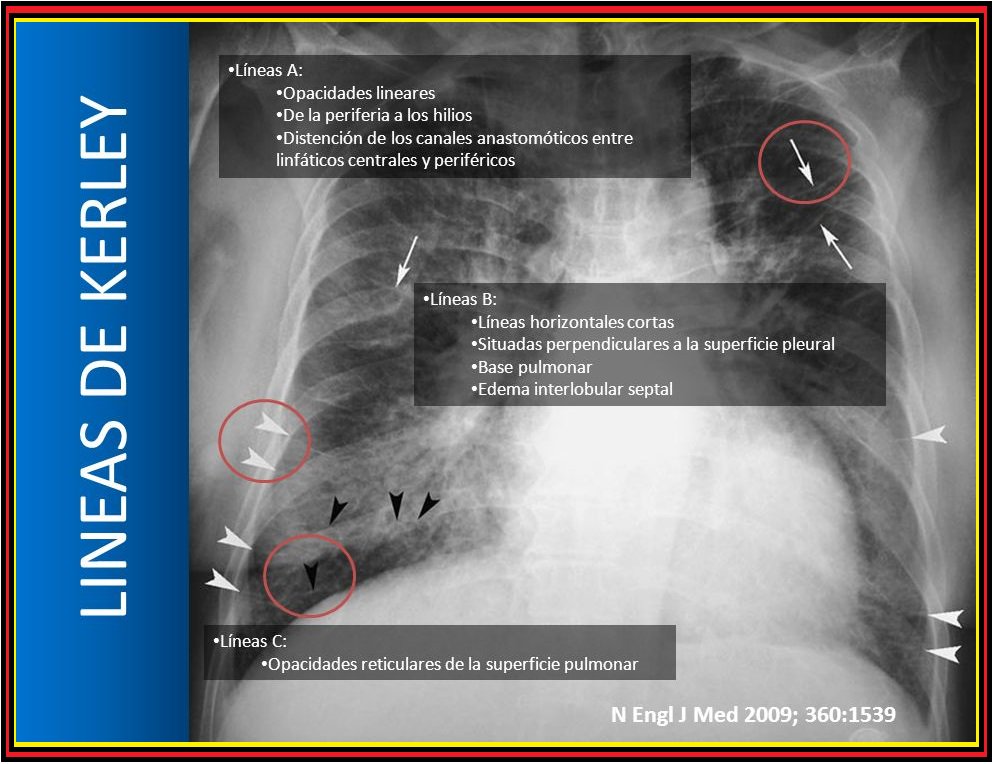

Línies de Kerley

Engrosament d'envans interlobulillars per edema, neoplàsia o inflamació.